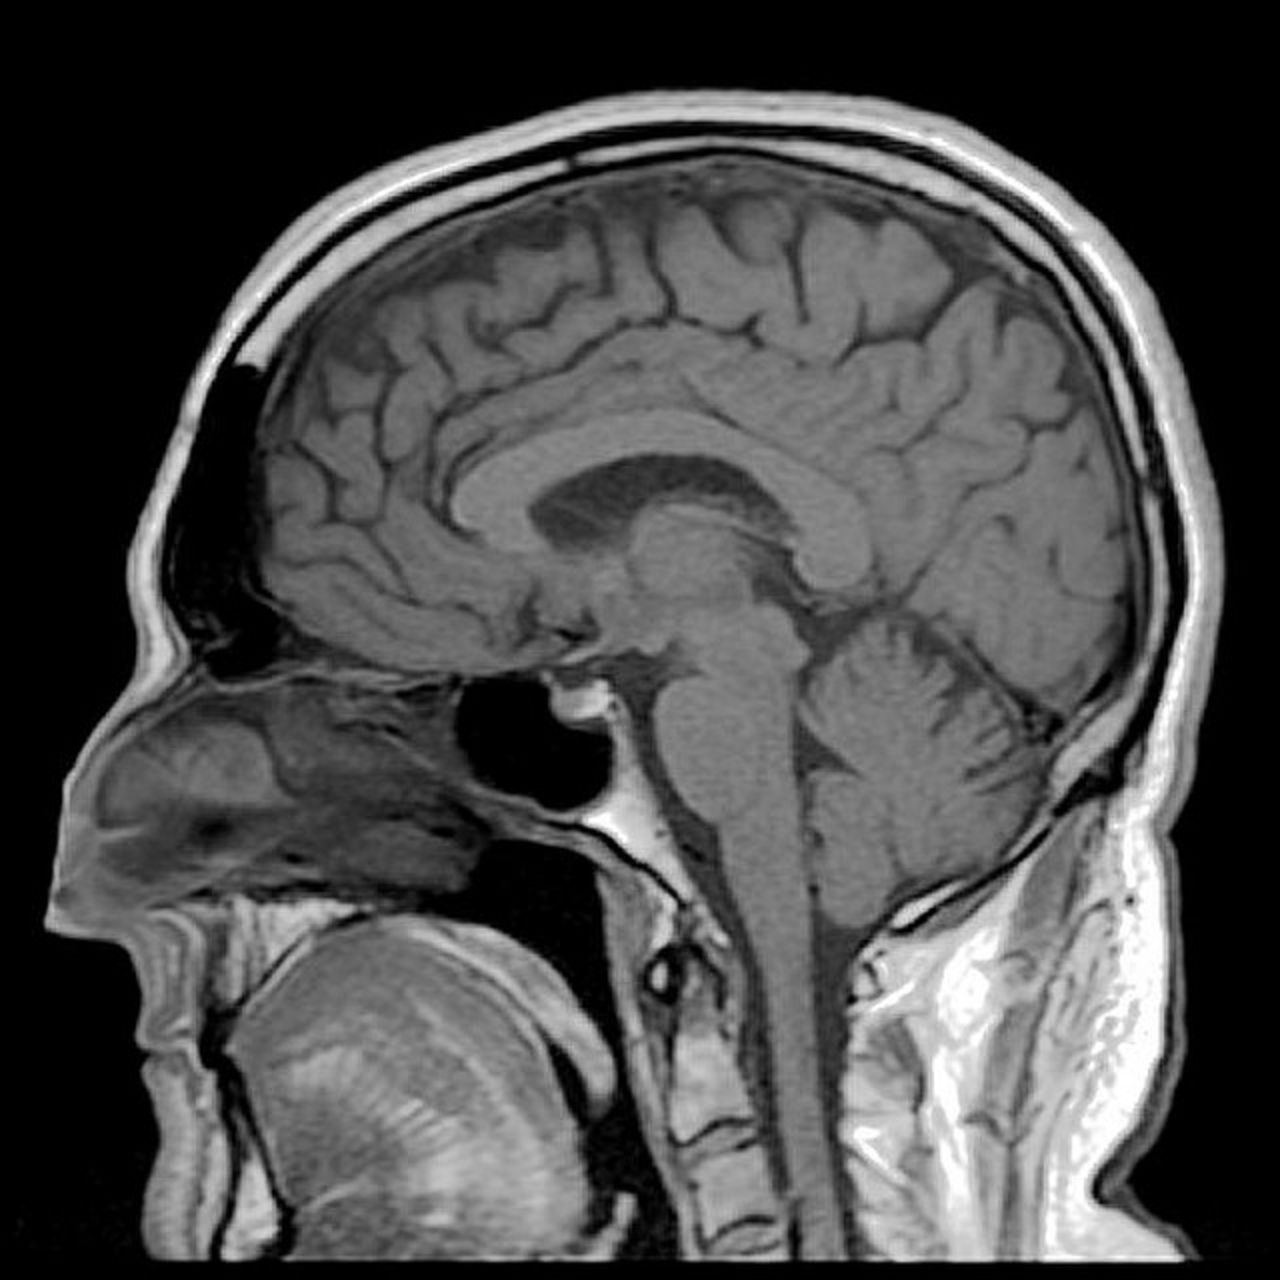

Ny teknik låter dig skriva med hjälp av hjärnan Perfekt för den som inte kan kommunicera som alla andra Ny teknik låter dig skriva med hjälp av hjärnan Foto: Reigh LeBlanc" target="_blank"> Forskare har tagit fram ett nytt tankeläsnings-system som för första gången kan låta vem som helst skriva ord och fraser, bokstav för bokstav, enbart genom att tänka. Det hela fungerar i realtid och du behöver varken säga något eller göra några som helst grimaser.Forskarna heter Bettina Sorger, Joel Reithler, Brigitte Dahmen och Rainer Goebel och de berättar att systemet kräver väldigt lite för att vara redo att börja användas. Systemet använder sig av funktionell magnetresonansavbildning eller fMRI som det förkortas som analyserar de hemodynamiska variationerna i hjärnan, alltså hur blodet rör sig där inne. Rörelserna är skapade av bilder vi får upp i huvudet och dessa knyts sedan till varje bokstav i alfabetet via en dator-algoritm.Systemet ska med framgång ha testats på patienter och det man gör för att det ska fungera är att man tittar på en skärm med alla bokstäver och sedan tänker på något en viss tid som man knyter an till en viss bokstav. När man sedan har gjort så för alla bokstäver är det bara att dra igång.Förutom att hjälpa folk med rörelsesvårigheter eller liknande skulle jag kunna tänka mig att använda tekniken till att skriva artiklar bara genom att ligga på soffan och stirra i taket, låter ju inte helt dumt. sciencedaily.com Vetenskap, Övrigt, funktionell magnetresonansavbildning, fMRI, forskning, hjärnan, skriva, teknik, utveckling Via Gizmodo